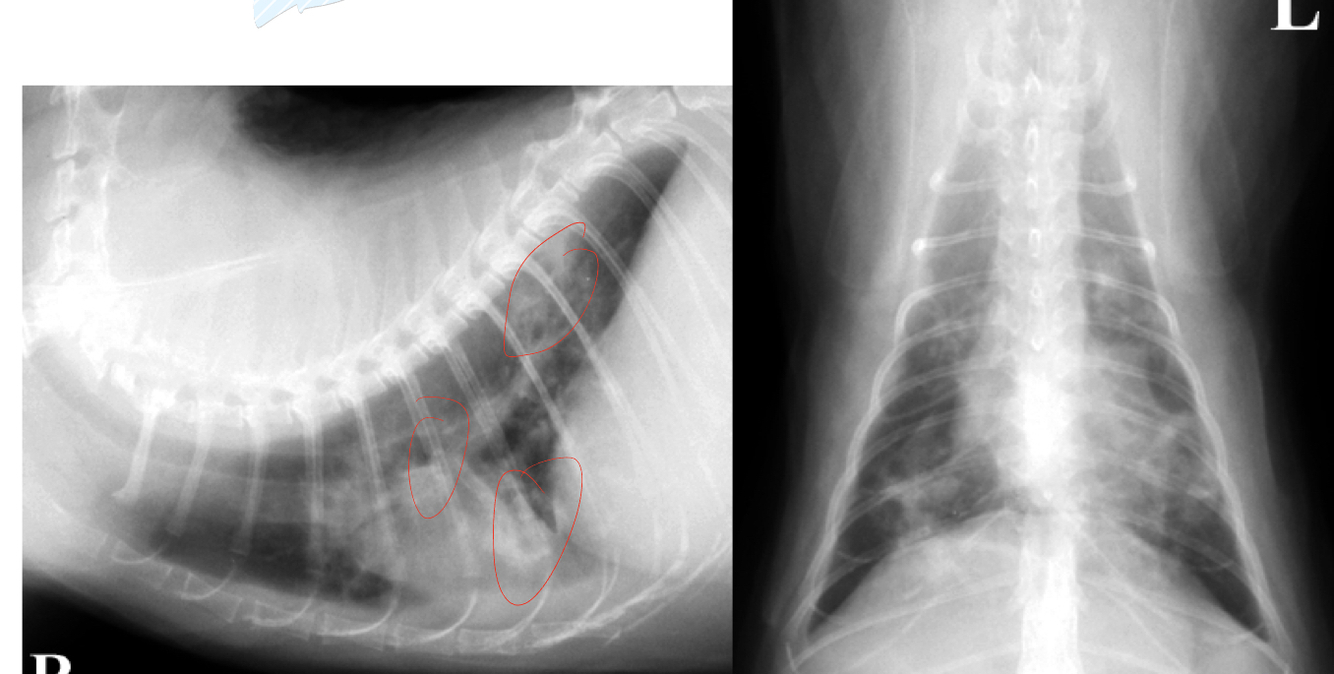

16

Q

what pattern

A

cranioventral

17

18

19

focal- mass under trachea